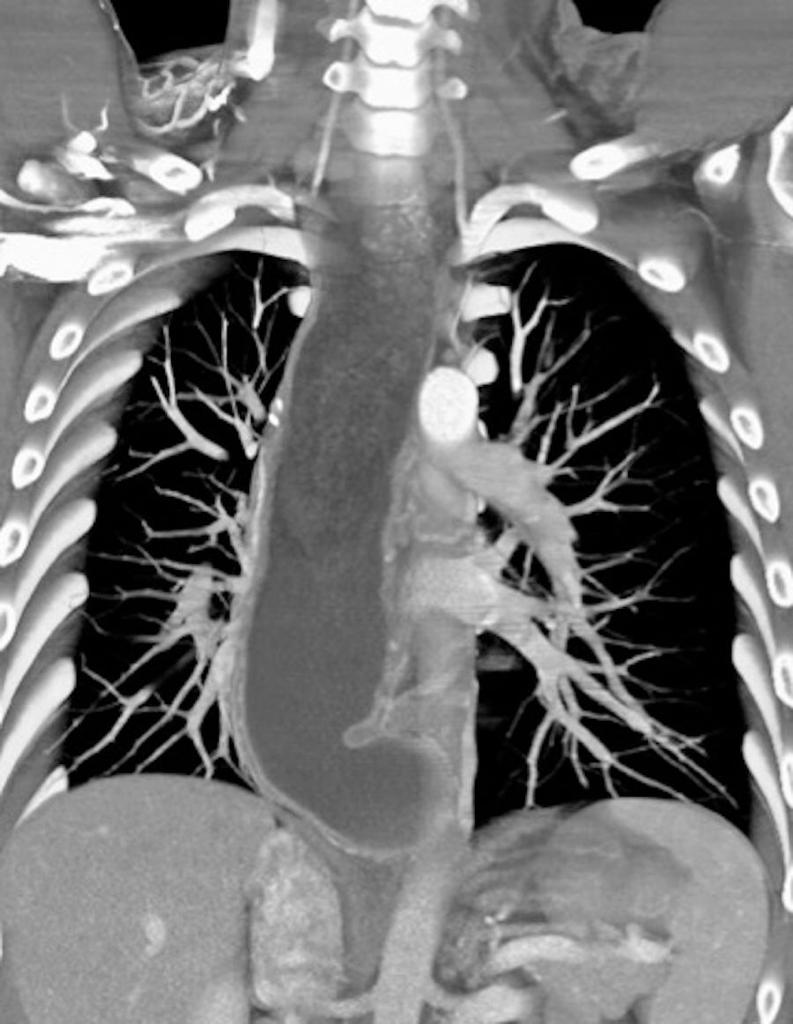

TC DE TORAX .

TC DE TORAX . La Acalasia es un trastorno poco frecuente, que dificulta el paso de alimentos y líquidos hacia el estómago. La acalasia se presenta cuando se dañan los nervios del esófago. En consecuencia, el esófago pierde la capacidad de empujar el alimento hacia...